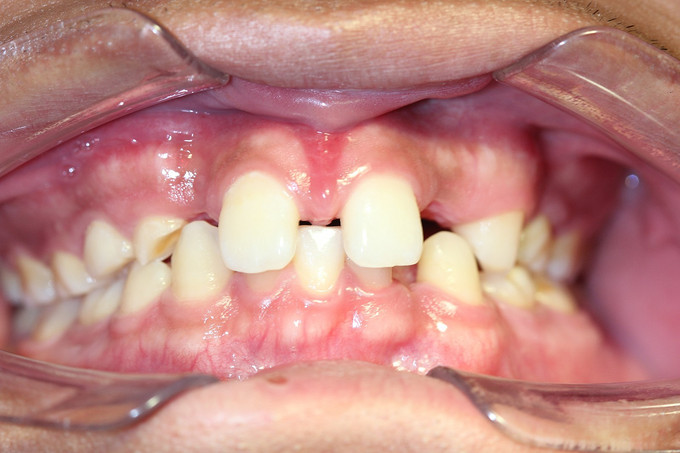

男 年龄16岁 右上恒牙2、3、4、5缺失,乳牙2、3、4、5滞留。 右下恒牙5缺失,乳牙5滞留。 左上恒牙2、3、4、5缺失,乳牙2、3、5滞留。 左下恒牙2、4、5缺失,乳牙2、5滞留。 诊断:恒牙先天缺失 治疗计划:a.乳牙治疗 b.唇系带手术 c.正畸治疗 d.种植体修复 现已经a、b两项治疗完成;因正畸难度较大,需要专家会诊共同完成!正畸治疗后再行种植修复。